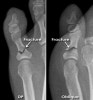

X-ray로 진단이 가능합니다.

X-ray : 지골 골절(Phalanx fracture)